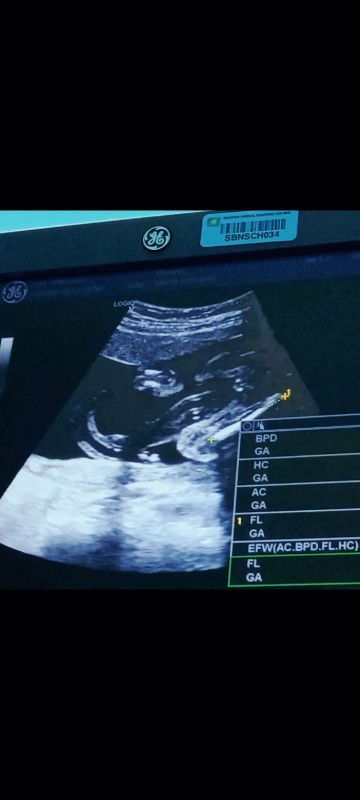

boy or girl ?

hi mommies, nak pinjam sat mata bole... ni boy ke girl eh ? 😂 #firstbaby #firstmom